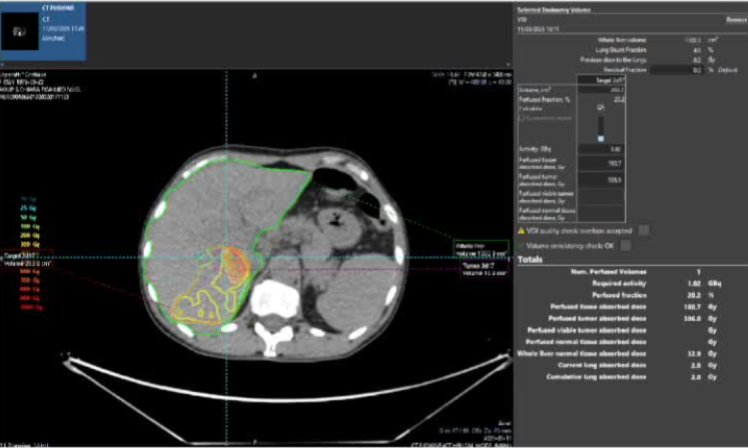

· 单中心、样本量小; 83 岁的女性,体重超标 40 毫米单发 ICC(S7-S8) 中肝静脉和右肝静脉浸润性,活检:非酒精性脂肪性肝炎(慢性肝病),马斯氏(MaS)病(30%)

考虑采用“三步策略 TARE→ PVE → Surgery”方案 剂量活性:1.56 和 3.16 GBq